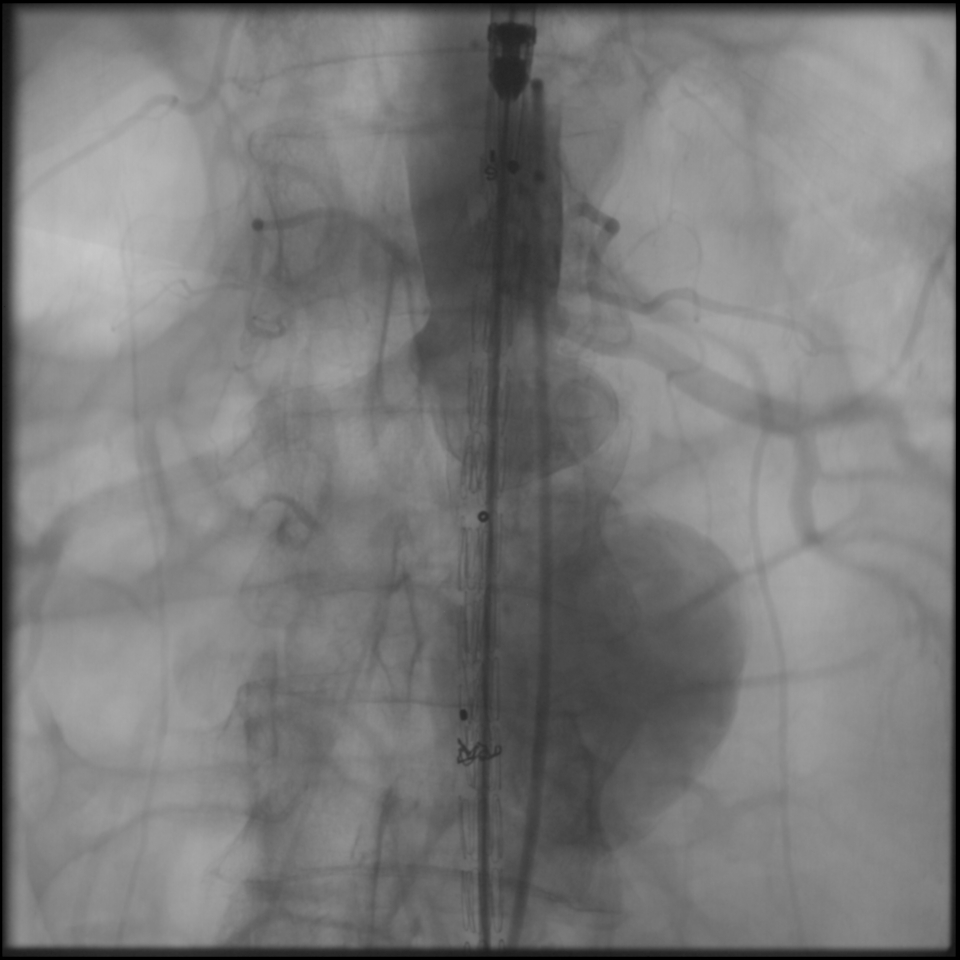

Abdominal (karın) Aort Anevrizmaları (karın içinde seyreden “şah damarının” balonlaşarak genişlemesi) yırtılarak ani ölüme yol açabilen istenmeyen bir durumdur. Sıklıkla ilerleyen yaşlarda batın USG’si yapılırken tesadüfen saptanan, şikâyete yol açmayan bir durumdur. Balonlaşmış bölge,ameliyatın kontrendike (yapılması için engellerin) olduğu durumlarda, anjiografik yöntemle kasık damarından girilerek stentlenir (EVAR); böylece ameliyatsız tedavi edilir.